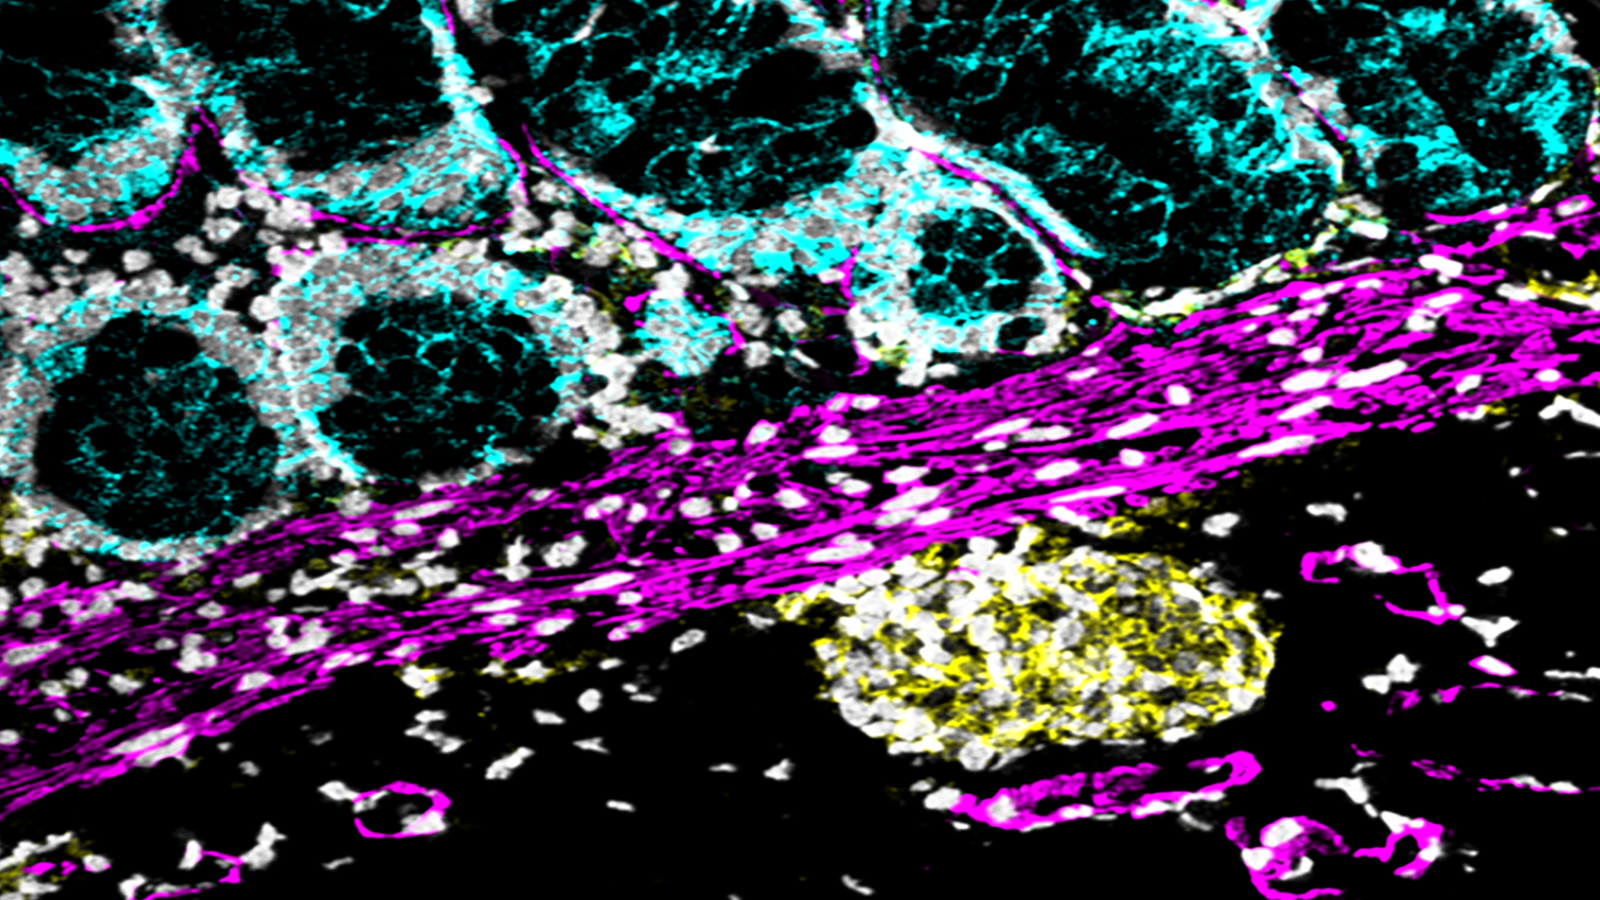

The lining of the uterus & fetal cells within & around maternal spiral arteries, courtesy of Dr. Michael Angelo at Stanford